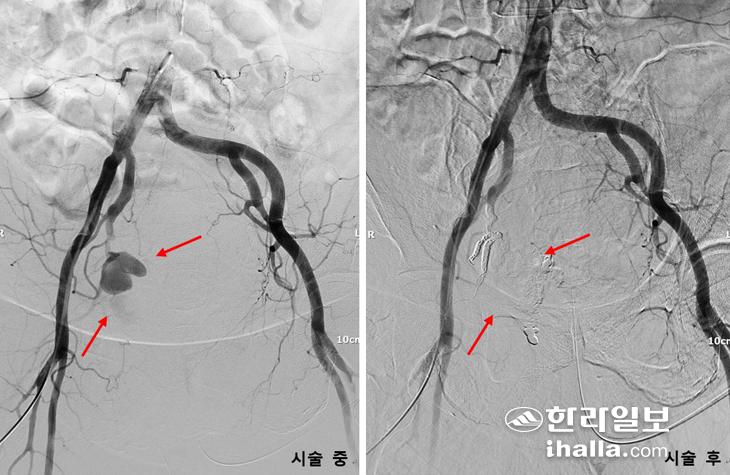

투석혈관내에 혈전을 제거하고 좁아진 곳을 넓히는 인터벤션 시술 전후의 모습. 제주대병원 제공

▶고인 것 빼주고=79세 남성 A 씨는 만성 콩팥병으로 4개월 전부터 오른쪽 팔로 혈액투석을 시작했다. 수술 후 얼마간은 동정맥루를 통해 투석이 잘 됐으나 어느 날 투석실에서 혈관이 막혀 투석이 잘 되지 않는다고 했다. 이학적 검사와 초음파 검사 등을 통해 동정맥루 투석혈관이 아직 충분히 성숙하지 못했으며 동정맥루 내에 혈전이 가득 찬 것을 확인할 수 있었다. 투석혈관에 가득 찬 혈전을 제거하고 좁아진 곳을 넓혀 미성숙한 동정맥루에 혈류량을 증가시켜 투석로를 성숙시키기 위해 인터벤션팀에 시술이 의뢰됐다. 시술 시간은 1~2시간 정도 소요됐으며 국소마취로 우측 내경정맥 부위를 마취 후 투석혈관을 직접 천자하지 않고 투석혈관 내에 혈전을 제거한 뒤 좁아진 곳을 넓히자 혈류는 재개통됐다.